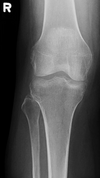

30

AP knee criteria (5)

open joint space (lat) tibial spines centred to tunnel lat tib plateau in a single line patella slightly lat to midline lat condyle of tibia superimposes half the fibular head

31

on an AP knee, if the fibular head is too high, what does that indicate

too much caudad angle

32

on an AP knee, if the fibular head is too low, what does that indicate

not enough caudad angle

33

correction

more caudad angle